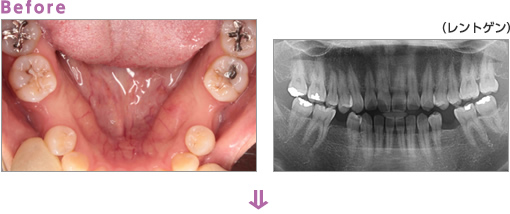

Before:右下の奥歯の脱離と銀歯の見た目が気になり来院。

After:銀歯をセラミックにしたおかげでお口がさらに明るい印象になりました。

治療費用

ジルコニアE-maxプレス ¥100,000/歯